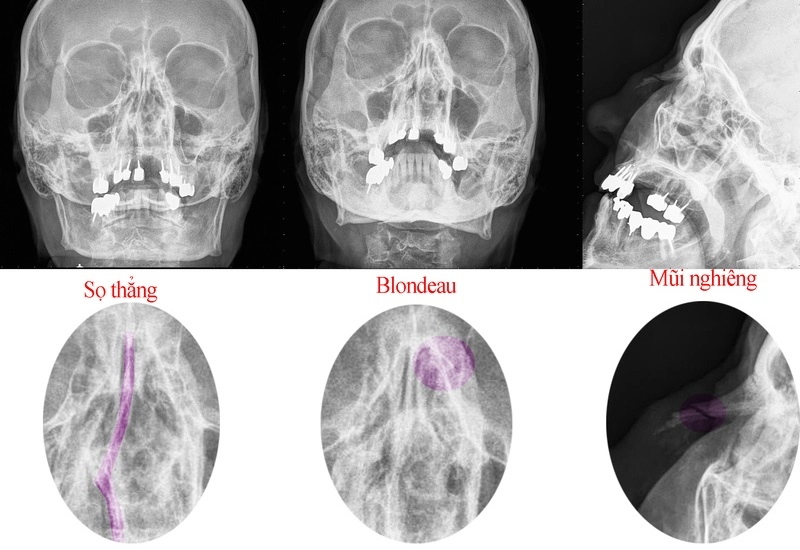

1.2. Chẩn đoán hình ảnh viêm xoang bằng chụp X-quang tư thế Blondeau

Tư thế Blondeau thường được áp dụng để phát hiện viêm tại xoang trán, xoang hàm và hốc mũi.

Ở tư thế này, tia X chiếu từ phía sau ra trước. Bệnh nhân nằm sấp, mở miệng tối đa, đồng thời mũi và cằm tiếp xúc trực tiếp với phim chụp.

Kết quả chụp cho thấy:

– Nếu có viêm xoang, hình ảnh X-quang thể hiện khe mũi bị mất hoặc hẹp do khối u hay cuốn mũi quá phát. Xoang hàm và xoang trán xuất hiện vùng mờ nếu có hiện tượng phù nề niêm mạc, dịch mủ tích tụ hay thoái hóa niêm mạc.

– Nếu nghi ngờ khối u ác tính, đặc biệt khi các thành xương bị mờ hoặc không rõ ràng, cần chỉ định thêm các kỹ thuật chẩn đoán chuyên sâu.

– Nếu xoang bình thường, hình ảnh hiển thị rõ ràng khe thở, ổ mắt, các thành xương cũng như xoang trán và xoang hàm đều sáng rõ.

Trong trường hợp nghi ngờ có dị vật trong xoang, bác sĩ sẽ chỉ định thêm chụp X-quang sọ nghiêng để xác định chính xác vị trí và kích thước dị vật. Nếu phát hiện khối u hoặc polyp trong xoang, có thể cần bơm chất cản quang để hình ảnh hiện lên rõ ràng hơn trên phim X-quang.